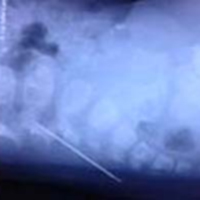

Tại Bệnh viện Việt Đức, các bác sỹ phải làm liệt tim, chạy máy thở nhân tạo cho bệnh nhân, sau đó mở tim, cầm máu. Khi mở vùng tim ra, tim của bệnh nhân đã rách nham nhở. Sau hai giờ đồng hồ phẫu thuật, các bác sỹ đã lấy ra được cây kim dài 4,5cm ra khỏi tim của bệnh nhân.